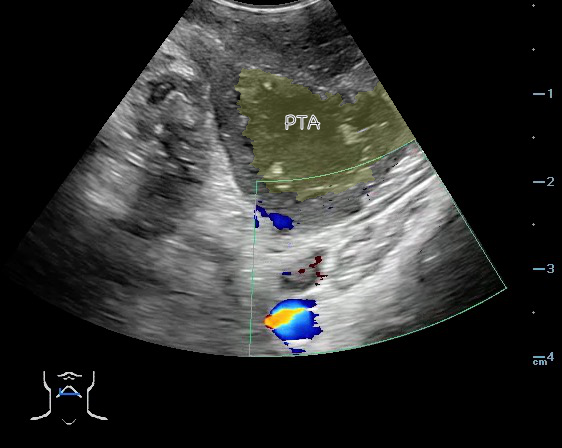

- Peritonsillar abscess is visualized as a hypoechoic or complex cystic structure

- The carotid artery is seen as an anechoic tubular structure along the posterolateral aspect of the tonsil on ultrasound. Its relationship to the abscess cavity should be determined. Color Doppler can help locate the carotid artery.

- Figure 47 and 48. PTA with color Doppler of carotid artery